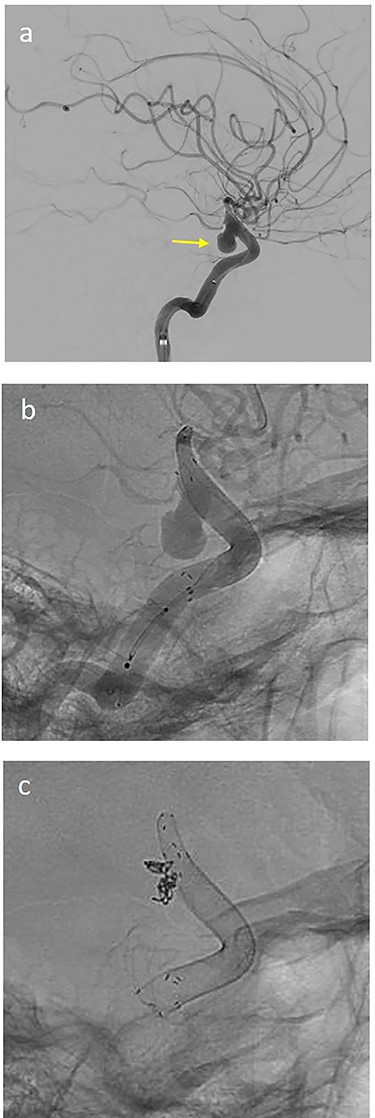

(a) lateral angiogram of left carotid artery showing ICA aneurysm before the second endovascular treatment; (b) Lateral view after implantation of two additional flow diverters (2× Derivo®—4,5/20); (c) Lateral view after additional coil embolization (HydroSoft™ 2/3 and 2× 1,5/2).

On the next day (Day 9 post-op), the patient suffered from acute and devastating headaches, with screaming and enuresis. An emergency computed tomography (CT) was carried out and displayed a prepontine and retroclival subarachnoid hemorrhage (Hunt & Hess Grade I), (Fig. 2). For further evaluation, a digital subtraction angiography (DSA) was conducted, and it showed a pseudoaneurysm of ophthalmic1/supraclinoid2/C23 part of the left ICA, which was directly treated by a flow diverter (Derivo®—4,5/20), with remaining rest flow (Fig. 3). The patient was transferred to the ICU, transcranial doppler sonography was performed and revealed normal flow. In the following course, the patient suffered from Terson’s syndrome and hyponatremia due to SIADH, but after clinical improvement, was transferred back to normal station after 10 days of post-operative monitoring. Furthermore, the patient was plagued with cephalgia and nausea, which could not be compensated with analgetics and antiemetics. On the 20th post-operative day after the epileptic seizure with postictal vigilance reduction, an emergency CTA was conducted showing progressive SAH (Fig. 4) and a growing pseudoaneurysm as well as generalized vasospasm with posthemorrhagic hydrocephalus. For an emergency CSF diversion, an external ventricle drain was placed. The repeated DSA showed a growing false aneurysm which was treated with two additional flow diverters (2× Derivo®—4,5/20) as well as coiling (HydroSoft™ 2/3 and 2× 1,5/2) by endoleak (Fig. 5). The vasospasms were treated by an intraarterial spasmolysis (Fig. 6).